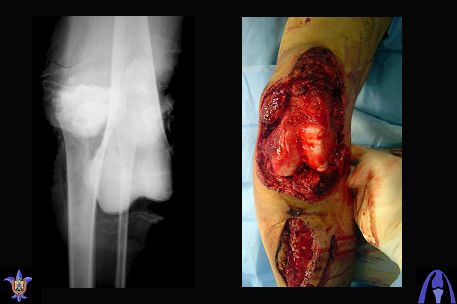

Снимки прошлых публикации из моего Power point

На ренгенограмме хорошая аппозиция костей коленного сустава, но надколенник находится подозрительно высоко, поэтому необходимо убедиться в отсутствии повреждения связки надколенника.

Наличие пульсации на конечностях еще не доказательство отсутствия интимальных повреждении сосудов, наблюдались вторичные осложнениия, поэтому важна консультация сосудистого специалиста.

Последующее два-три месяцев проводим ЛФК сустава,

потом на основании стабильности сустава решается

необходимость оперативного вмешательства.

Общепринятые последовательности реконструкции,

поэтапные восстановление PCL плюс медиальная или PCL плюс латеральная, хотя множество случаев когда связки срастались в течение 6-7 недель, больные восстанавливали движения сустава без оперативного вмещательства.